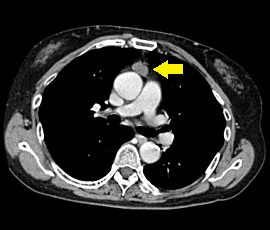

[気管支原性嚢胞] 手術:胸腔鏡下縦隔腫瘍手術

CT画像